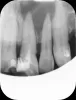

Судя по данному снимку, очаг разряжения костной ткани (очаг воспаления) находится как в области 2.1 зуба, так и 2.2 -го.

Таким образом, возможно, имеет смысл попробовать вскрыть и пролечить и 2.2 зуб.